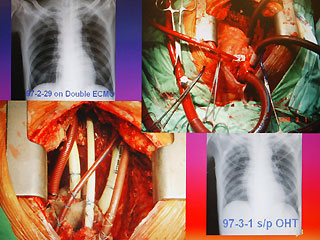

病人陈先生感染细菌性心内膜炎,造成心脏破坏(左下方),进行全心脏摘除术,并放置叶克膜(右上方)体外维生系统以维持生命。

报道说,现年60岁的陈先生,2月初因发现感染细菌性心内膜炎,致使整颗心脏感染严重,从奇美医院转到台大医院之后,经家属同意,决定进行全心脏摘除,然后置入叶克膜维持生命。陈先生最后靠着叶克膜撑过16天,奇迹式活下来,于今天顺利出院。

台大医院心脏血管外科教授王水深率领团队执行这个艰难的手术。他说,陈先生心脏的三尖瓣膜等处已被细菌噬光,无法修补,最后“走投无路”之下,决定先摘除心脏,而家属的决定也需要相当大的勇气。

王水深说,摘除心脏时没人能保证有心脏可换,而靠叶克膜体外维生系统通常也只能维持7天左右,但陈先生靠着两套叶克膜奇迹式的撑过16天,克服感染及排斥,又能幸运的等到心脏捐赠者,他强调,翻遍文献可说史无前例。(周先)